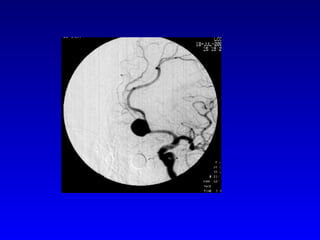

Angiography In proven SAH- 4 vessel angio(DSA) to identify source and r/o multiple aneurysms Initial arteriogram negative in upto 16% of  SAH MRA detects 90% of saccular aneurysms of >5mm Spiral CT angio detects 85% of saccular aneurysms

Angiography In provenSAH- 4 vessel angio(DSA) to identify source and r/o multiple aneurysms Initial arteriogram negative in upto 16% of SAH MRA detects 90% of saccular aneurysms of >5mm Spiral CT angio detects 85% of saccular aneurysms